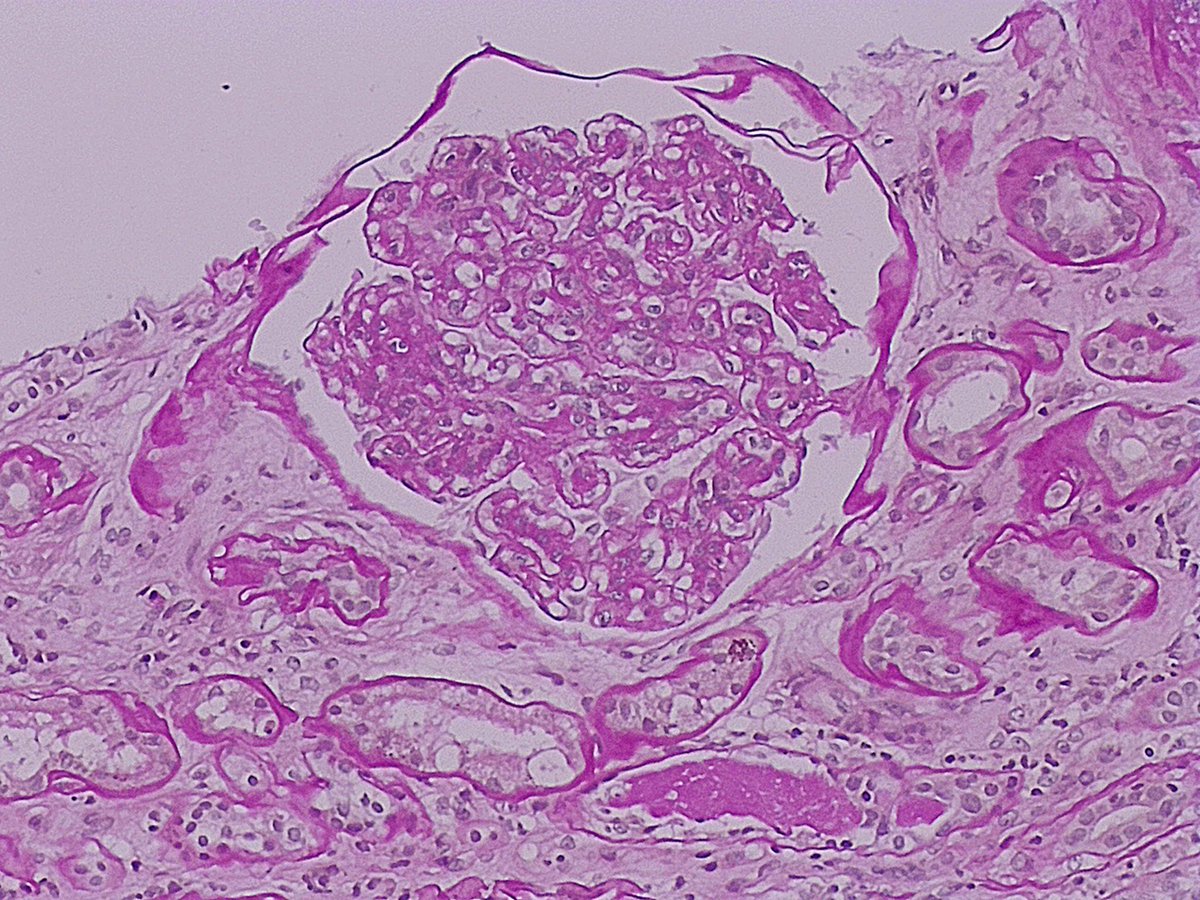

Mujer 👩 47 años Con App: Fibromialgia ????? Debuta con HTA hace 2 meses Proteinuria 24h : 2083.0 mg Ana: positivo Resto inmunológico : negativo Biopsia Renal :

8

9

52

Vamos a hacer una Biopsia ! Y de repente ! Que es esooooooooo?